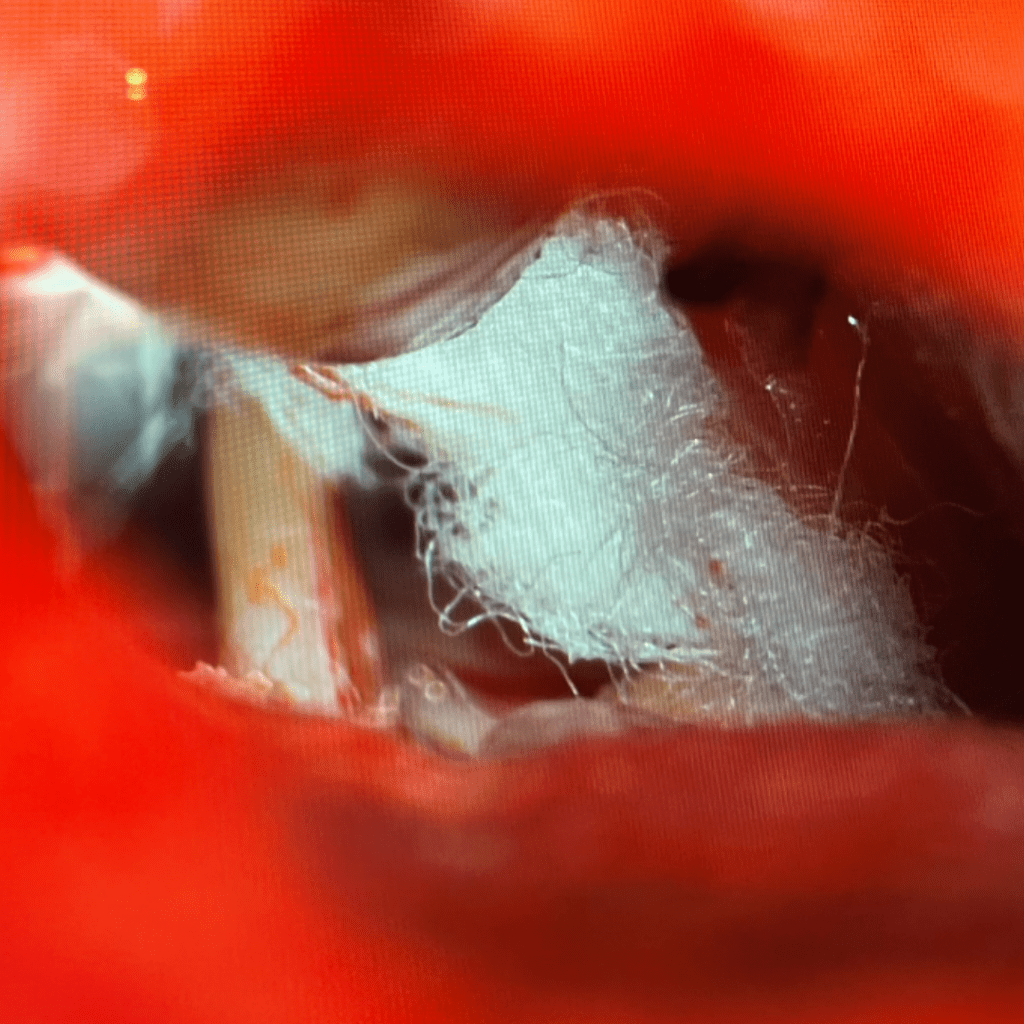

In this case, a loop of the superior cerebellar artery was causing significant compression and distortion of the trigeminal nerve root (Figure 3). The superior cerebellar artery is the usual offending blood vessel in cases of trigeminal neuralgia. Using micro-dissection techniques with appropriate micro -instruments, the artery is dissected off the nerve, and very small pieces of teflon felt (a non-absorbable material) are used to keep the artery from recompressing the nerve. The final image under the microscope shows the trigeminal nerve root fully decompressed, with resumption of normal anatomy (Figure 4).